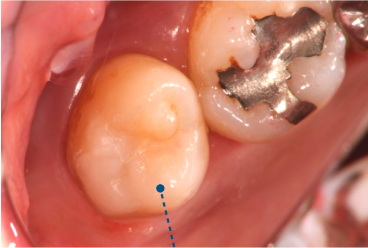

レジン充填法(保険・自費)

• 治療前

• 治療後

一般的に虫歯治療の際に利用する「詰め物」は銀歯をイメージされるかと思いますが、当院では白い素材(レジン)を利用します。次のような特徴があります。

✅「ゲル状」なので削る量を最小限に抑えられる

✅「1回の来院」で治療が終了

保険適用の素材と、レジンにセラミックの材質を入れ込んだ、より審美性が高い素材を利用した自費治療(16,500円~/税込)の2つから選択できます。